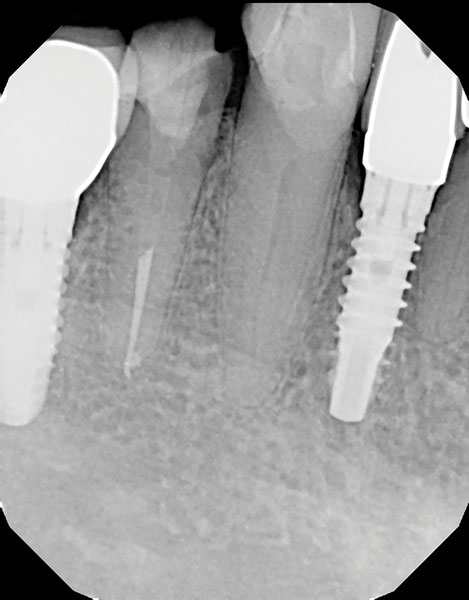

Un cemento de resina de curado dual / material de acumulación (Core-Flo DC Lite, BISCO) se mezcló y se colocó primero en el poste y la manga. A continuación, se colocó una pequeña cantidad de cemento en el canal y se insertaron rápidamente el poste y el manguito. El poste se empujó firmemente hacia abajo en el canal y se sujetó mientras se empujaba la manga hacia abajo con un par de pinzas de algodón. Luego se colocó resina adicional para rellenar y acumular hasta el nivel deseado, y se mantuvo una luz de curado sobre el aspecto oclusal durante 40 segundos (Figura 6). Después de que el área se aisló de la humedad y se dejó fraguar por completo durante 3 minutos, se tomó una radiografía del poste y el manguito con la acumulación (Figura 7), se realizó una preparación de la corona (Figura 8) y se fabricó un provisional para el paciente (Figura 9). Regresó 3 semanas después para que se asentara la corona final (Figura 10).

Imagen 7. Radiografía del poste adherido y la formación de manguito y muñón.